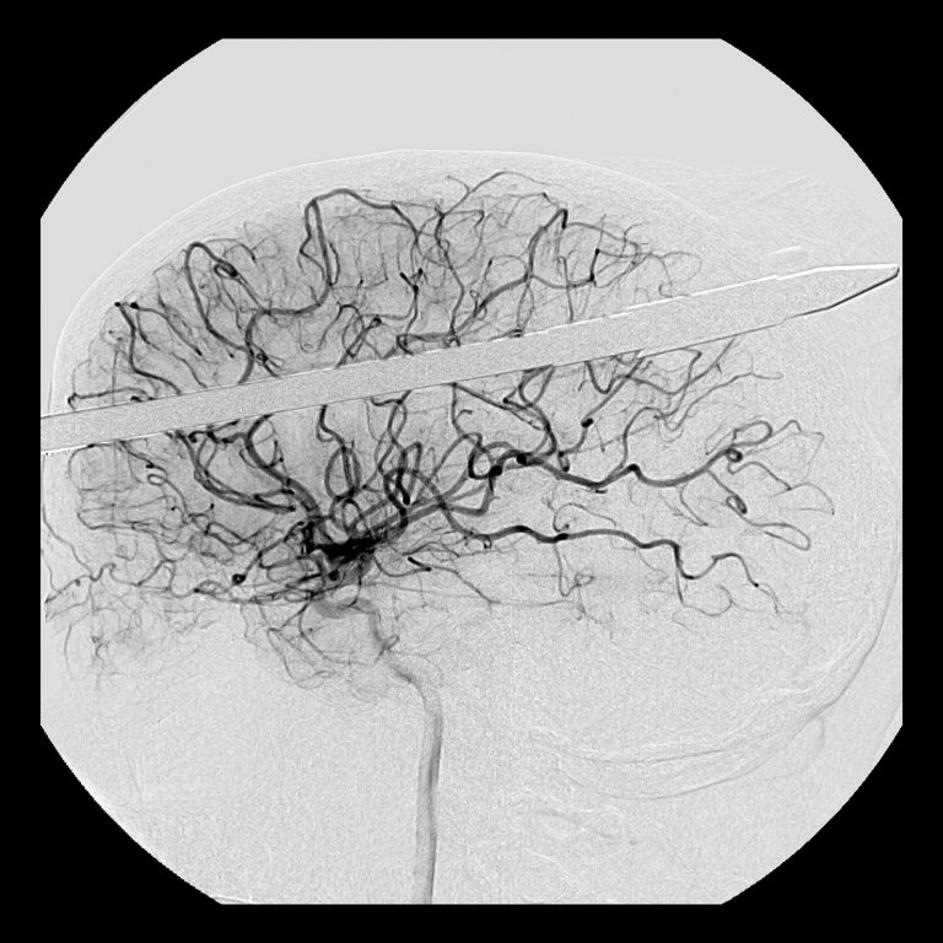

Glavo mu je preluknjala harpuna

Yasser Lopez